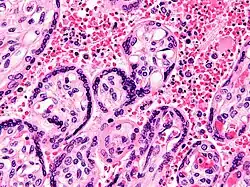

Insuficiência hepática

É pouco comum a ocorrência de insuficiência hepática provocada por malária, sendo geralmente o resultado da coexistência com outras condições que afectam o fígado, como a hepatite viral ou qualquer doença crónica do fígado. A síndrome é por vezes denominada “hepatite malárica”. Embora a sua ocorrência seja ainda considerada rara, a hepatopatia malárica tem vindo a aumentar, sobretudo na Índia e no Sudeste Asiático. A presença de doenças hepáticas em pacientes de malária aumenta a probabilidade de complicações ou morte.[43]

A infecção com P. falciparum pode provocar malária cerebral, uma forma grave de malária que envolve encefalopatia. Manifesta-se através do branqueamento da retina, o que pode constituir um sinal clínico auxiliar para distinguir a malária de outras causas de febre.[18] Pode também ocorrer esplenomegalia, dor de cabeça intensa, hepatomegalia, hipoglicemia ou hemoglobinúria com insuficiência renal.[13] Em casos de malária durante a gravidez, entre as complicações graves estão a morte do feto ou da criança, ou peso à nascença inferior a 2,5 kg,[19] em particular na infecção por P. falciparum, mas também por P. vivax.[20]